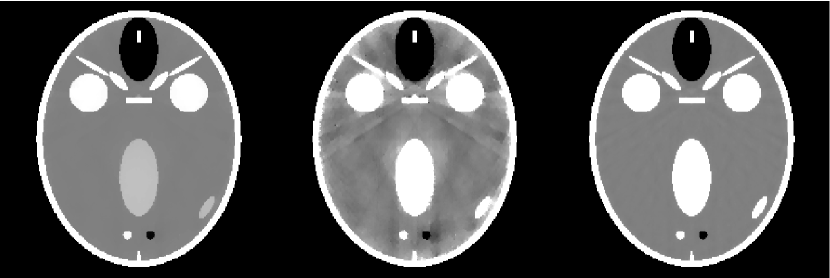

Another way to evaluate images is by visual comparison. The reconstructed images in Fig. 9 are shown for a range in showing the transition to accurate image reconstruction by -TV. That the -magnitude and -roughness show strong artifacts for this range is expected as their corresponding image RMSEs are at the level of the minimum phantom contrast level. Interestingly, the microcalcifications can be identified and well-characterized in all reconstructions, although more clearly with more views. It may be argued that, from a utility point of view, that views would suffice if we are solely interested in the microcalcifications and disregard the prominent artifacts of the background image. The ROI of the -TV reconstructed images are shown with a narrow gray scale window in the bottom row to reveal the high level of accuracy at . We emphasize here that our goal is not to go into a discussion about different artifacts but simply support our conclusions on undersampling from Sec. V-C by illustrating the behavior in the transition region around .

The breast phantom study is repeated employing a variation of the FORBILD head phantom [46] which is highly sparse in the gradient-magnitude image. The present version of the phantom, which is seen in Fig. 11, does not have the ear objects of the original phantom, and the contrast levels have been increased so that the minimum gray-level contrast is the same as for the breast phantom. The gradient magnitude sparsity is , or approximately a quarter of the breast phantom. In Fig. 11, the obtained for -magnitude, -roughness and -TV are shown as function of with and .

For -TV, on the other hand, the step-like transition occurs already at , for which the reconstruction is shown in Fig 11. We expect that this phantom would be recovered exactly at in the limit , leading to an admitted undersampling with respect to exact reconstruction of a factor of approximately . Stable reconstruction occurs at , i.e., an undersampling also of a factor with respect to stability.

Interestingly, the exact reconstruction result hints at the existence of a simple relation between sparsity and admitted undersampling. Compared to the breast phantom, there is a gain in undersampling by . In comparison, we note that the change in gradient magnitude sparsity relative to the breast phantom is . That is, reducing the sparsity by a certain factor leads to an improvement in the admitted undersampling by the same factor. This result, if shown to hold, could be important for practical application of CS-inspired sparsity-exploiting methods, since it provides quantitative insight into how many views would suffice for reconstructing images of given sparsity. Another conclusion that can be drawn is that simulations with images of too low sparsity compared to a realistic level in the imaging scenario of interest are bound to yield over-optimistic promises of undersampling potential. This could have been anticipated but the result establishes this expectation quantitatively.

We also note that while we may have exact reconstruction of the head phantom at and the reconstructed image at appears very accurate in the gray scale window, it is in fact not an exact reconstruction. By narrowing the gray scale to , also shown in Fig. 11, prominent artifacts become visible. This underlines that exact reconstruction is not the relevant notion for a fixed, non-zero . Instead, stable reconstruction, at , yields an accurate reconstruction, and for the present case already at (also shown in Fig. 11) the artifacts are reduced to a negligible level in the gray scale window.